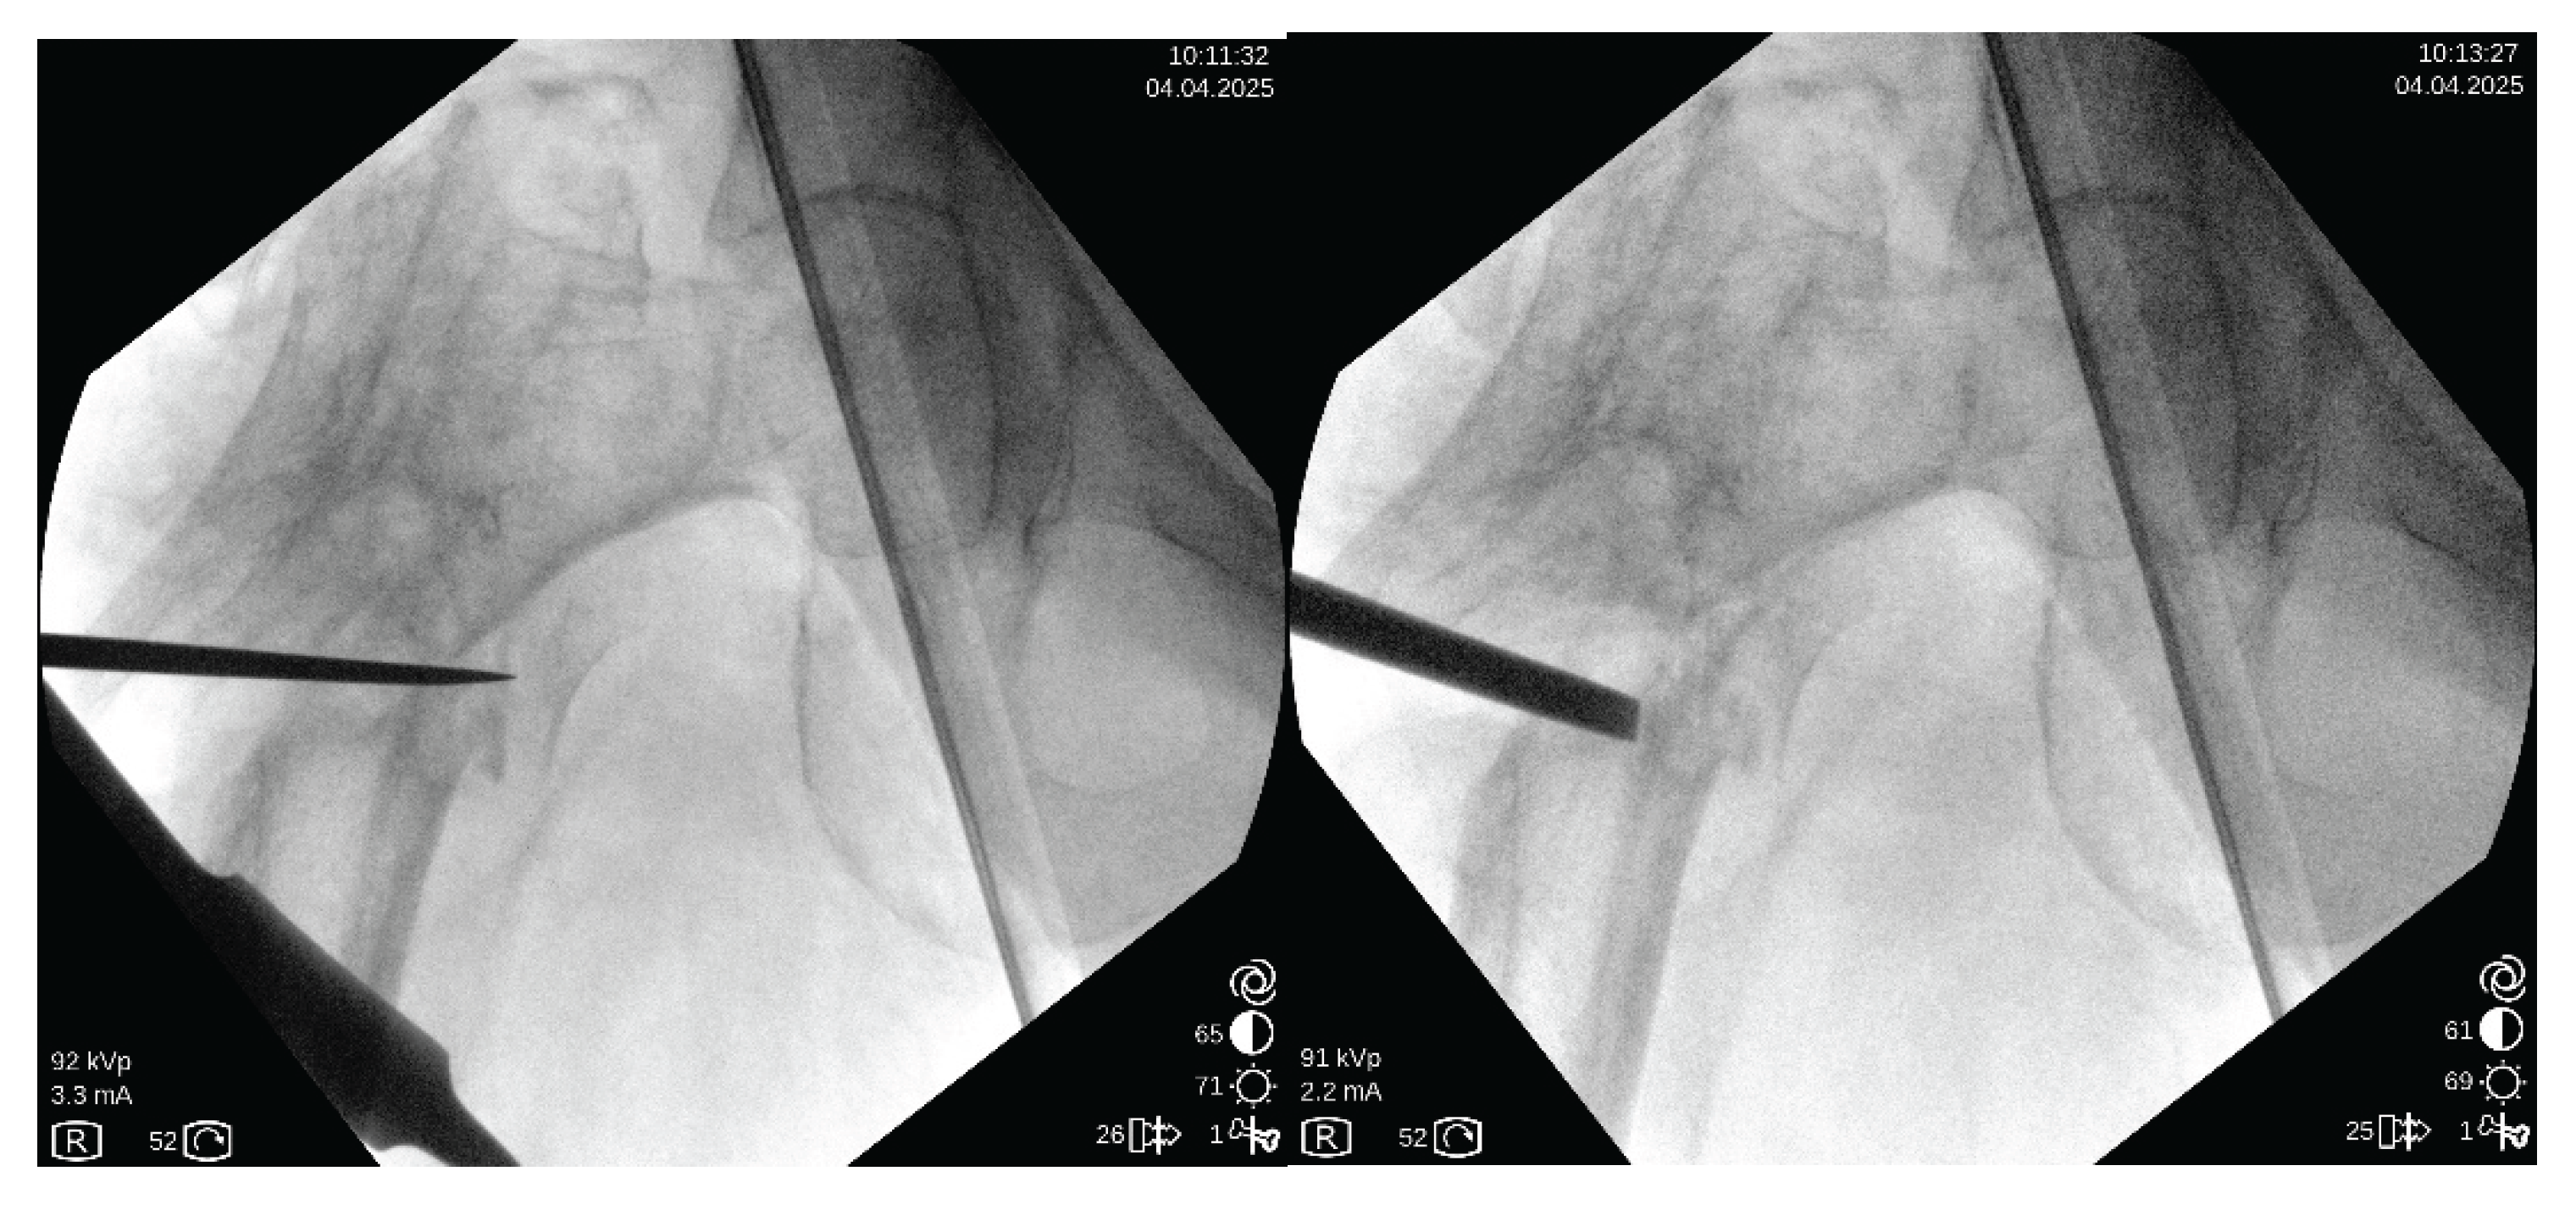

Figure 5. chisel decompacting the nonunion area: left) chisel introduced till medial cortex; rigth) opening of the medial part of nonunion.